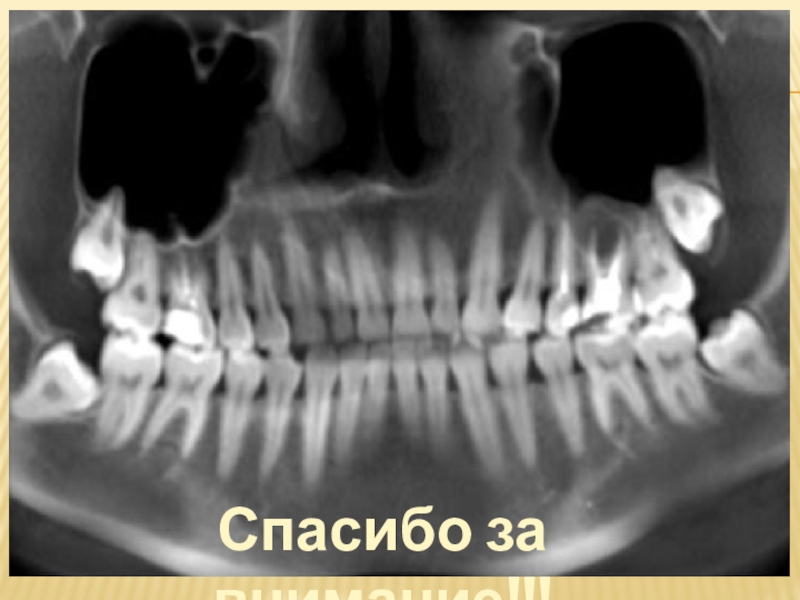

Для постановки диагноза и составления плана лечения используются следующие лучевые

методы исследования:

1) дентальная рентгенография

2) боковая рентгенография нижней челюсти

со стороны локализации патологического процесса;

3) ортопантомография

4) спиральная компьютерная томография;

5) конусно-лучевая компьютерная томография

Наиболее часто в практическом здравоохранении используются ден-тальная рентгенография и ортопантомография, однако оптимальными ме-тодами исследования при болезнях прорезывания являются ортопантомо-графия и конусно-лучевая компьютерная томография коническим пучком .

Эффективные дозы облучения при различных методах лучевой диагностики заболеваний челюстно-лицевой области следующие:

‒ при дентальной рентгенографии — 0,01–0,02;

‒ ортопантомографии — 0,07–0,15;

‒ спиральной компьютерной томографии с 3D-реконструкцией — 1,2–2,3;

‒ конусно-лучевой компьютерной томографии — 0,036